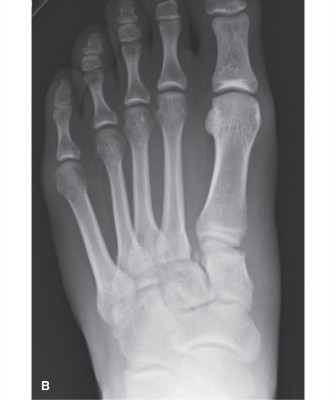

Second Ray Reduction (The Cornerstone):

This is the most critical step.

- Restoring the MC-2MT alignment: Focus on anatomical reduction of the second metatarsal base into its recess within the cuneiforms. Use reduction clamps, bone-holding forceps, or joy-stick K-wires into the metatarsal head for traction and manipulation.

- Address any dorsal, plantar, or lateral displacement. This reduction should be meticulously performed to ensure there is no residual gapping or malrotation.

- Comment: This image could depict an intraoperative fluoroscopic view demonstrating the successful anatomical reduction of the second metatarsal base to the medial cuneiform with provisional K-wire fixation, highlighting the key alignment before definitive hardware placement.

- Assessment: Throughout reduction, constantly monitor alignment using fluoroscopy (AP, oblique, and lateral views). Ensure restoration of the medial and intermediate cuneiform-second metatarsal spaces, symmetrical Meary’s angle (lateral view), and the appropriate metatarsal cascade.